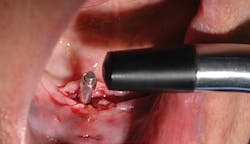

After the fabrication of full upper and lower immediate dentures, the patient underwent extraction of the remaining teeth and the placement of eight immediate dental implants (Hahn Tapered Implants, Glidewell; figure 8).

At the time of placement, ISQ readings were taken. Though the primary stability was high in these implants, the decision to allow them to integrate prior to loading was made, as each individual implant would be subjected to forces and they were not splinted. After insertion, 3-mm healing abutments were placed on all the implants except tooth No. 3, as that implant had a much lower initial stability reading. On the lower arch, 3 mm healing abutments were placed on all implants except for No. 22 due to stability. The dentures were relieved and delivered to the patient.